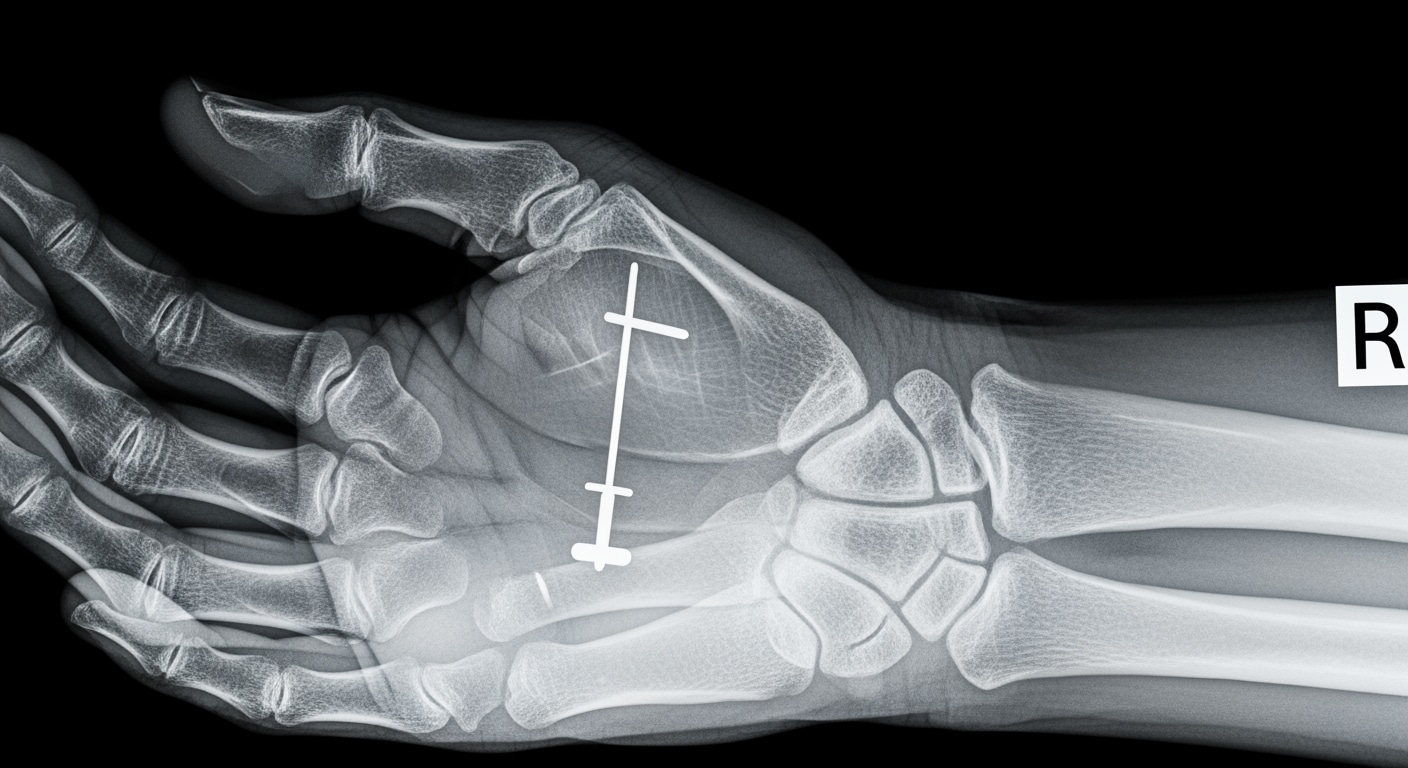

Priority ER's diagnostic capabilities for emergency x-ray services exceed Joint Commission standards for emergency departments[14], featuring digital radiography systems typically found only in major trauma centers. Our x-ray system produces images with 99% diagnostic accuracy compared to conventional film standards, enabling detection of subtle fractures, pneumothorax as small as 5%, and foreign bodies requiring surgical removal[15]. The integration of picture archiving and communication systems (PACS) allows instant image transmission to consulting orthopedic surgeons when complex fractures require specialized surgical planning.

Advanced imaging diagnostics through our comprehensive capabilities include not just standard x-ray views but also CT scanning, ultrasound, and specialized radiographic series for complex trauma evaluation. For patients with multi-system injuries, our imaging department performs trauma series protocols, dedicated spine imaging, and advanced reconstructions automatically, crucial for identifying life-threatening injuries that standard urgent care x-rays cannot fully assess. This technology gap explains why the American College of Emergency Physicians recommends freestanding ERs over urgent care for all significant trauma requiring immediate comprehensive imaging.